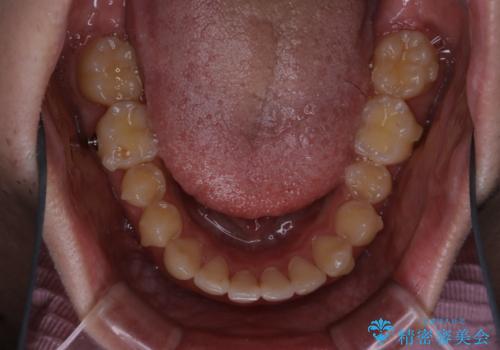

- 上の前歯が見えすぎて気になるとご相談にいらした方です。インビザラインにて前歯の圧下を行うことで歯の見え方の改善し、同時に奥歯の噛み合わせも改善を行いました。

インビザラインを正しく使用して頂けたおかげで、比較的難しいとされる歯の圧下も補助装置を使用せずに行うことが出来ました。上の前歯のラインが整ったことで笑った時の口元の印象を改善させることができ、大変喜んでいただけました。